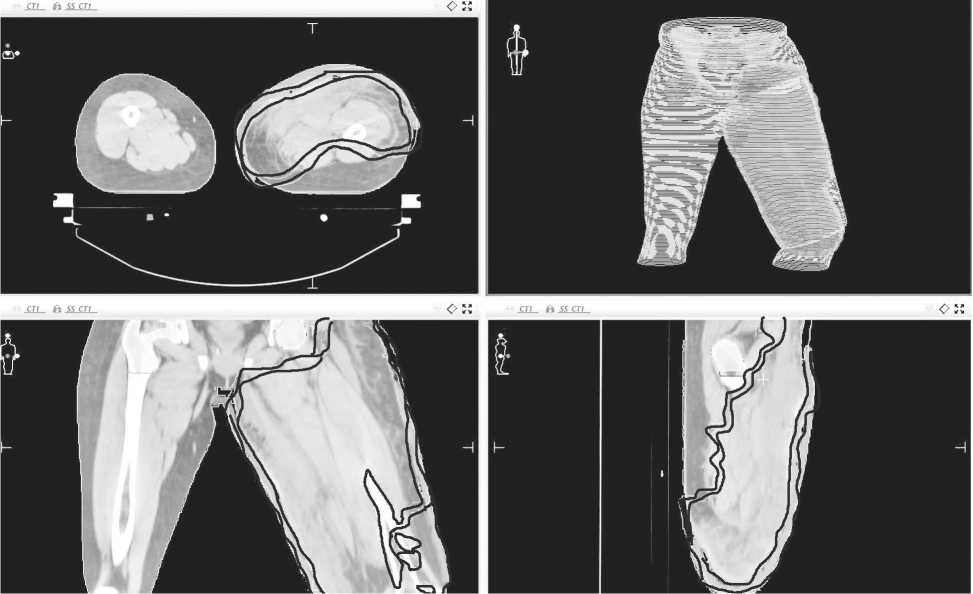

Рисунок. 3. Этап подготовки к дозиметрическому планированию лучевой терапии, оконтуривание

Учитывая отсутствие ответа на проводимое ле карственное лечение , объём поражения , болевой синдром , было принято решение о проведения пал лиативного курса 3D- конформной лучевой тера пии . Лечение проводили на линейном ускорителе электронов «Elektra Precise» тормозным излучением энергией 6 МэВ с применением тканеэквивалентно го болюса толщиной 1 см ( Рисунок 3 и 4) на область зоны поражения левого бедра , РОД 2 Гр до СОД 44 Гр с применением индивидуальных фиксирующих и формирующих устройств .